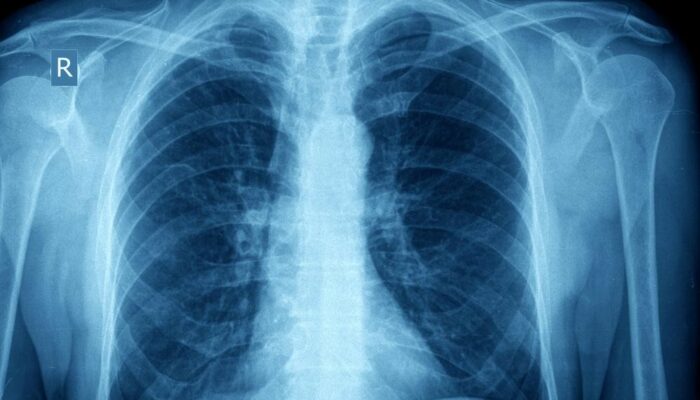

Asthma takes place in two forms; acute and chronic. Acute asthma, known as an asthma attack is an episodic event that occurs due to an asthma trigger. Chronic asthma develops due to the changes that occur from prolonged inflammation over time.

When a patient comes into contact with an asthma trigger, a chain reaction of events occur that leads to an asthma “attack.” The exposure to the trigger will cause the muscles that surround the airways to “clamp down” or contract, thus narrowing the spaces for air to travel through.

It is believed that patients always have some degree of inflammation in the lungs that make them more sensitive triggers. Chronic inflammation over time can lead to changes in the structures of the lungs and increased mucous production. Proper control of asthma can limit these effects.